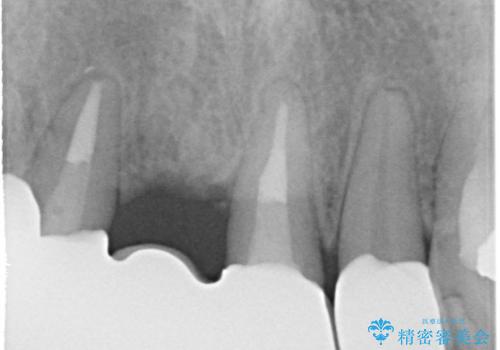

レントゲンを撮影すると保存が難しい歯がありました。

①保存不可の歯の抜歯・根管治療

- 根管治療により類似の全ての症例の問題が解決するわけではなく、症例はあくまでも一例です

- 根管治療により痛みや腫れがひかない事や、術後に痛みや腫れが生じる事、治療によるファイル破折やパーフォレーションなどの偶発症、術後の歯根破折を生じる可能性もあります